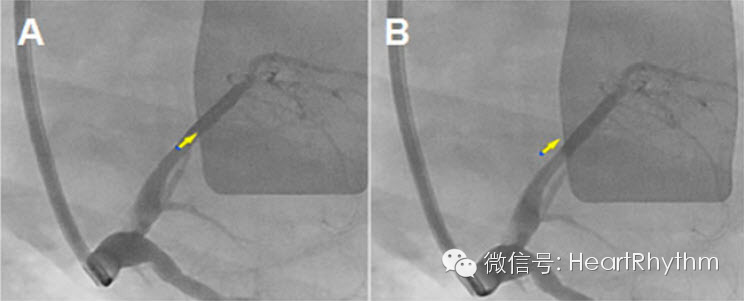

图3. 在事先录制的电影片段中显示传感器投影。A图中传感器图标与事先录制好的静脉窦造影边界相吻合,距离标记为0;B图中传感器图标已轻微超出血管造影边界,需要测量两者间的距离以便分析定位准确性。